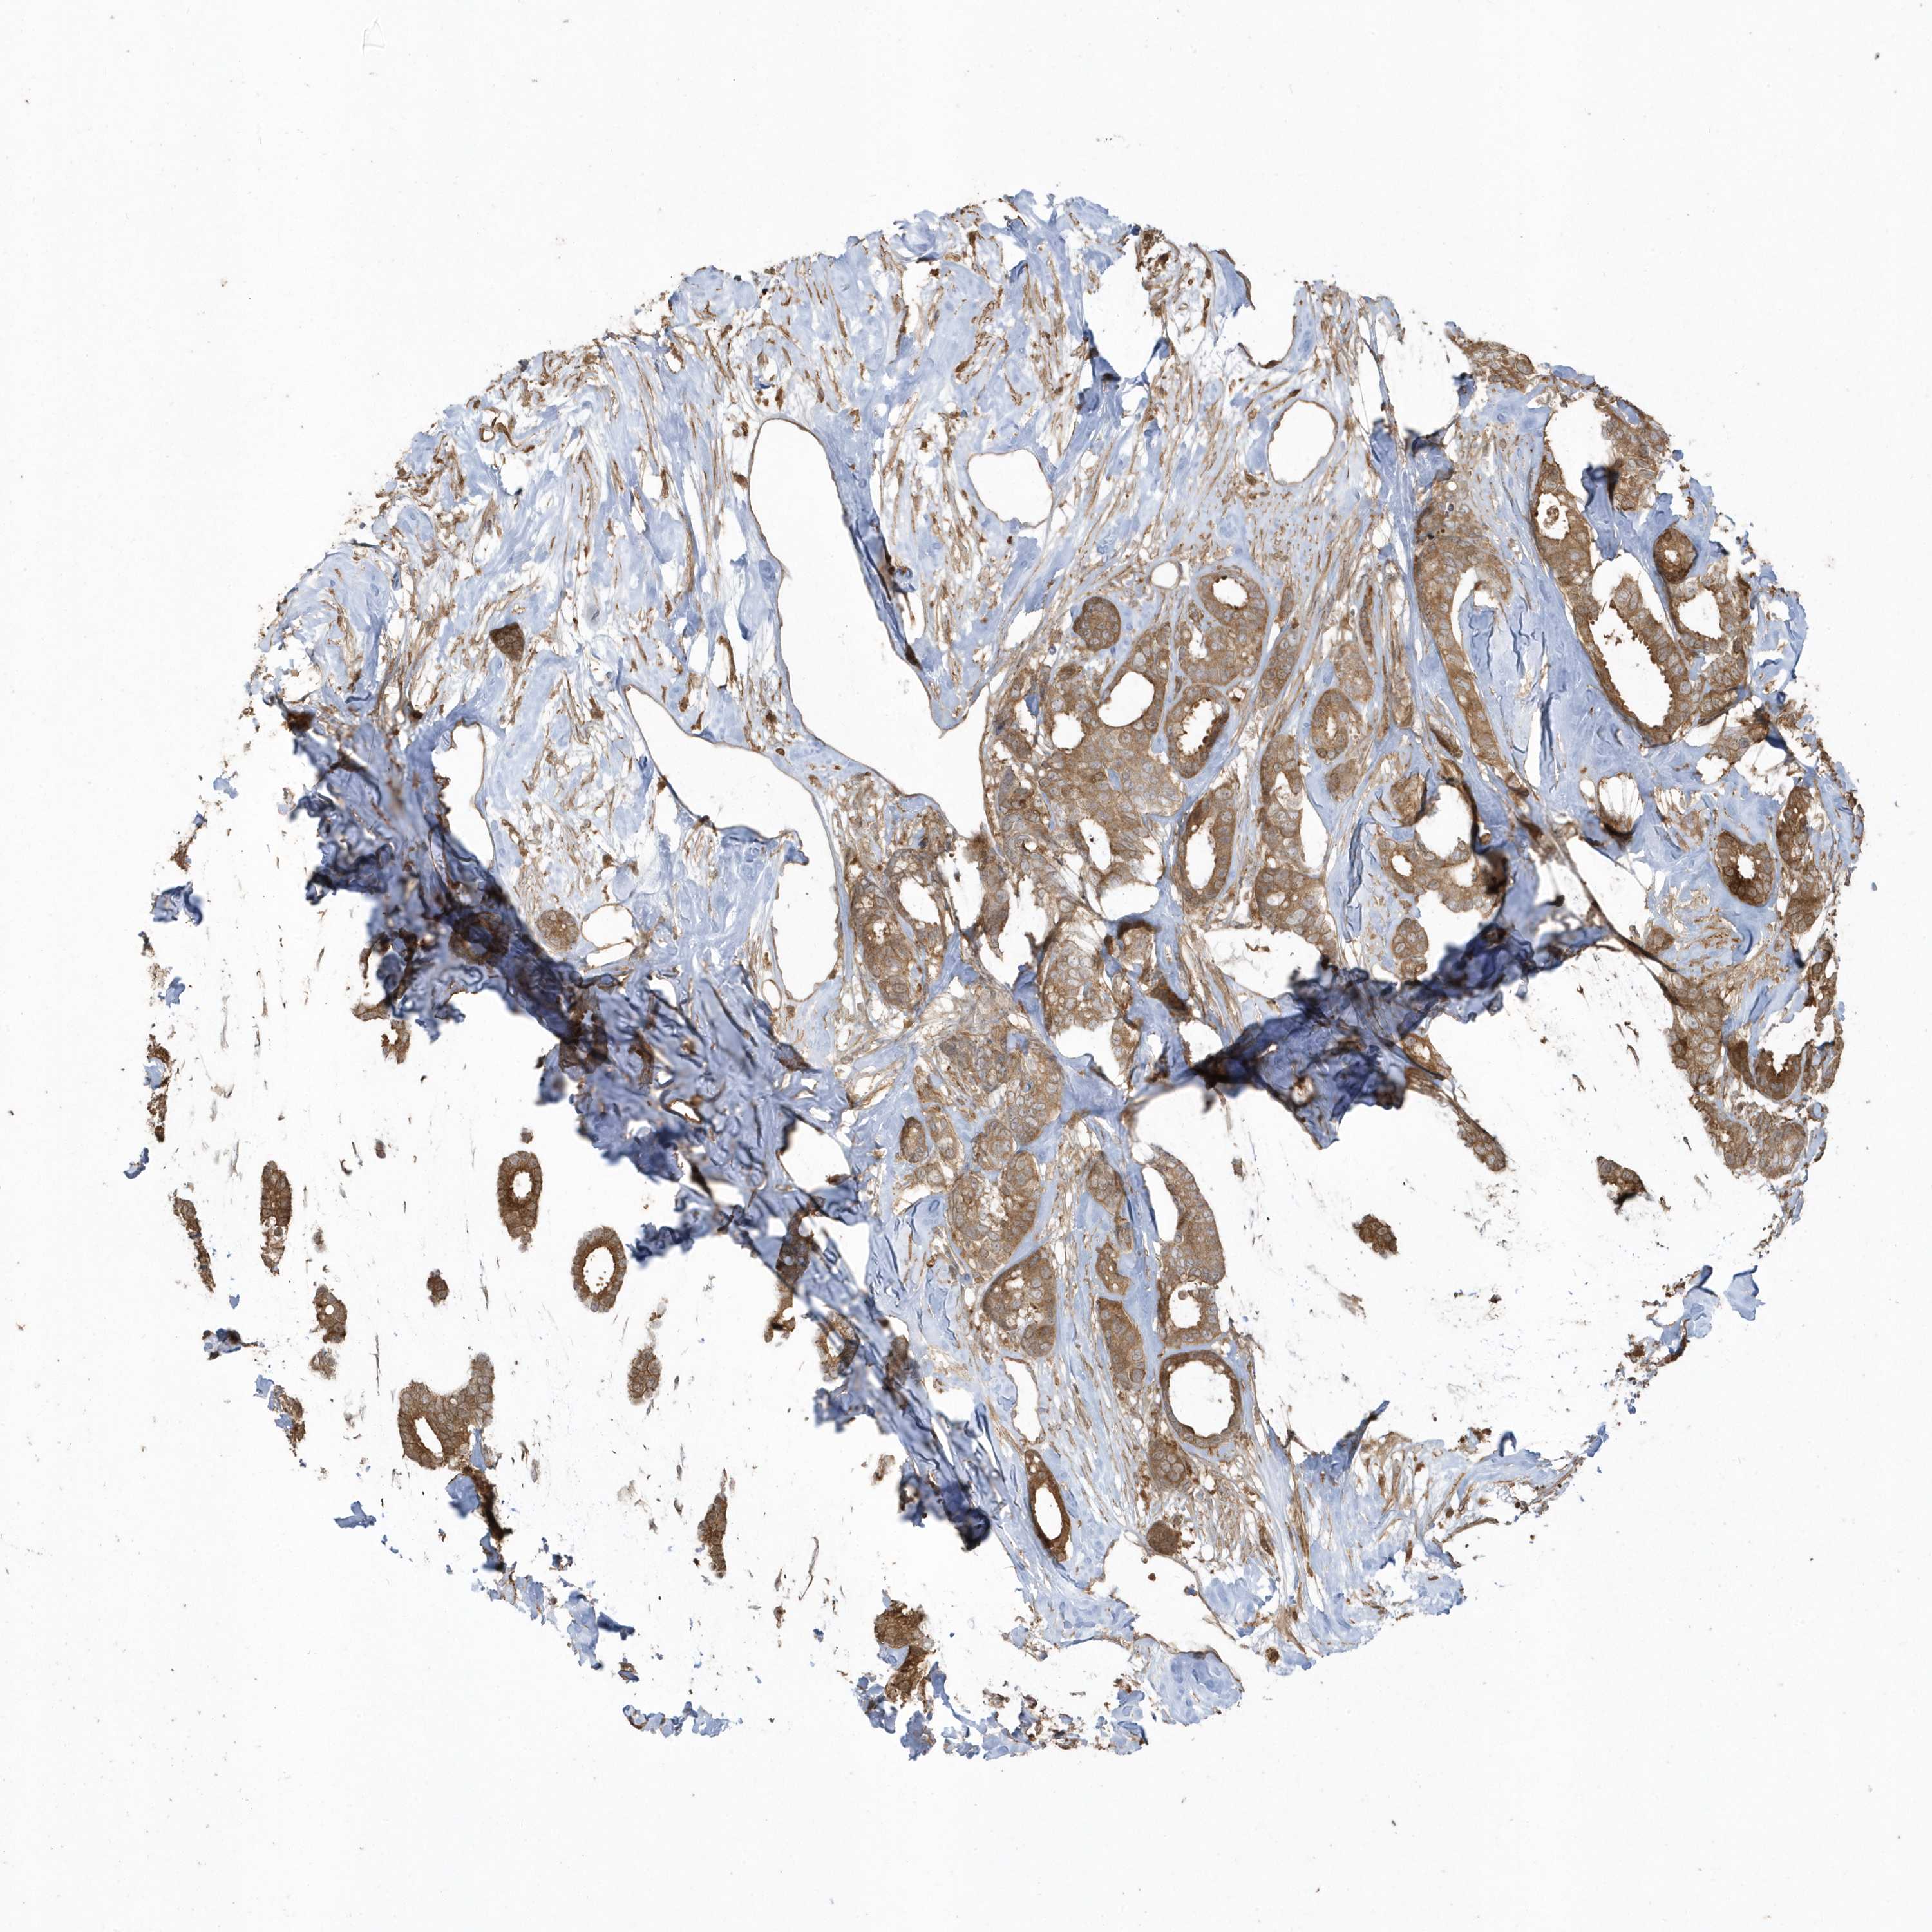

CANCER BREAST CANCER Show tissue menu

BRCA TCGA BRCA VALIDATION PROTEIN EXPRESSION

ANTIBODIES